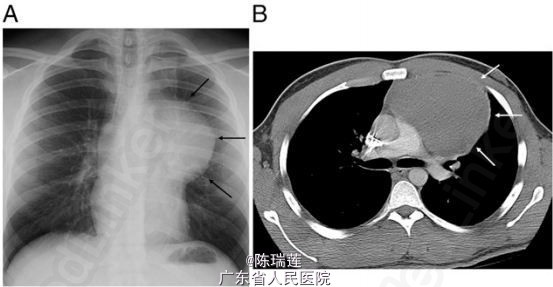

生命征未见异常,体查结果均正常,包括无睾丸病变,无淋巴结病变和无甲状腺肿大。胸部听诊,呼吸音清,无心脏杂音。腹部体查无肝脾肿大和无血管杂音。无皮肤病变。 胸片可见左纵隔肿物(图 1A)。进一步采用 CT 增强扫描可见前纵隔有一 10×7cm 的密度均一的肿物(图 1B)。 实验室检查:乳酸脱氢酶,α- 胎蛋白,β2 微球蛋白,促甲状腺素,甲状旁腺素,钙离子浓度,黄体生成素、卵泡刺激素均正常。淋巴瘤和 HIV 检测均阴性。 组织病理学可见肿瘤细胞形态均一,细胞核呈圆形,染色质均一。在坏死区域,每 10 个高倍视野可见 7 个细胞分裂象(图 2)